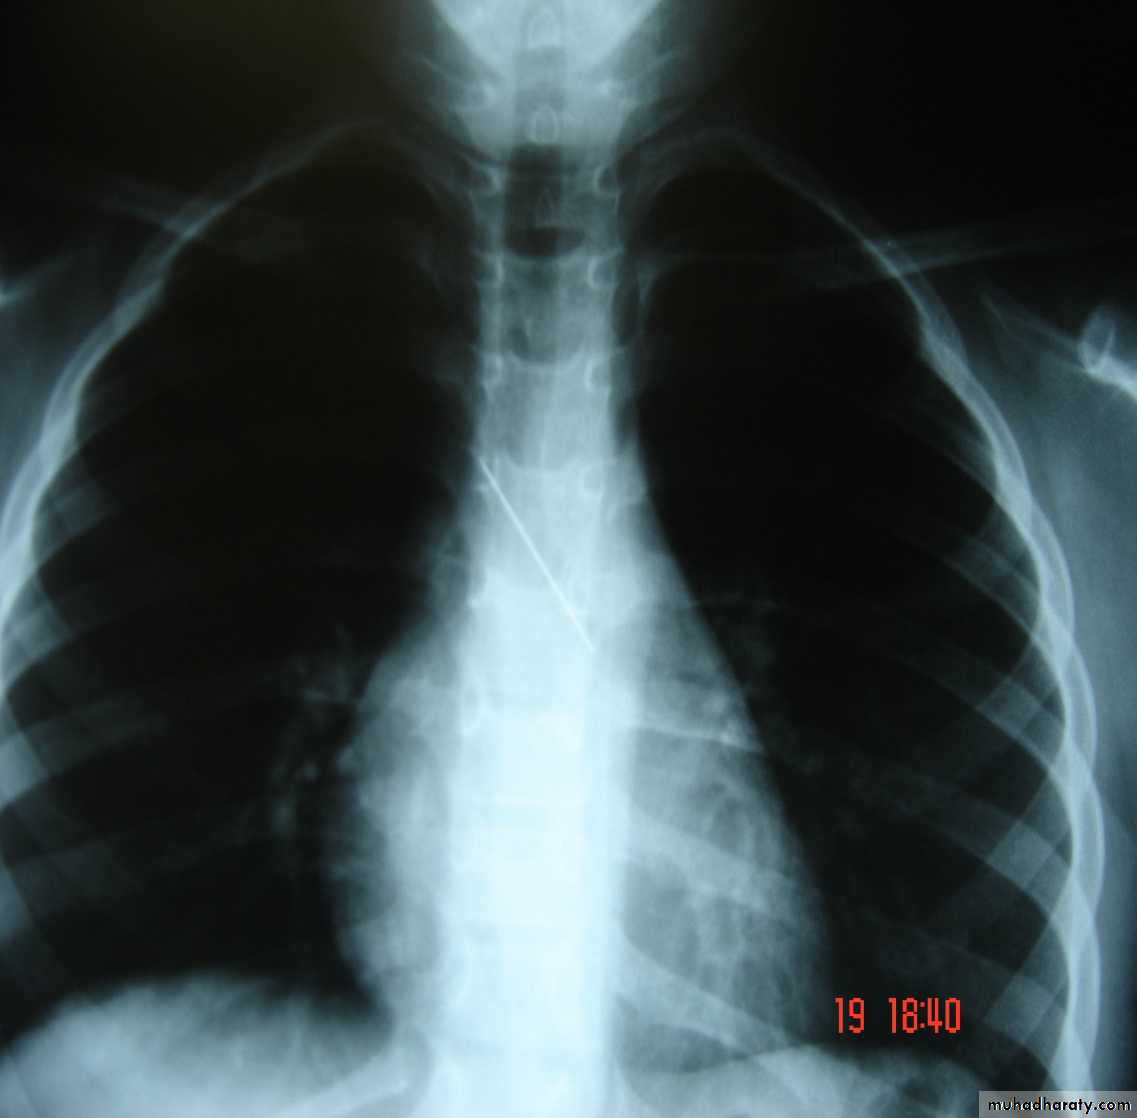

• Pulmonary Echinococcosis (Hydatid Cyst)

• Hydatid disease of the lung is caused by the small tape worm (Taenia Echinococcus ) or (Echinococcus Granulosis) .Hydatid cyst means cyst full of water .It has a life cycle between dogs & sheep .Parasites in the elementary tract of the dog shed ova that excreted in the dog faeces , contaminated the food of the sheep in which hydatid cyst will develops in the viscera . Including the lung .Infected sheep when slaughtered and its entrails are eaten by dogs , the life cycle is completed .When a human being hands or food become contaminated with canine fecal material containing ova which will be ingested .The parasitic larva burrow through the gastric mucosa and are carried to the liver in the portal venous circulation where most of them filtered out to form hydatid cyst of the liver , some escape the liver & lodge in the lung to form one or more hydatid cyst which grows slowly or rapidly over years .

• The cyst consists of a germinal layer & cyst fluid containing broad capsule & scoleses . A cellular white hyaline layers are laid down outside the cyst so that the cyst is enclosed by a laminated cyst membrane .As the cyst enlarged , it usually reaches the pleural surface . Compression of the lung tissues produces a thin fibrous layer of atelectatic lung tissue around the cyst (capsule , pericyst or adventia)

• Clinical Manifestation

• A-Asymptomatic• Any smooth homogenous opacity of uniform density with clear cut border and little or no reaction around it on a chest X-Ray is a hydatid cyst unless proved the other wise .

• Radiological Findings

• 1-Smooth homogenous opacity (Intact H.C).• 2-Partial rupture (per vesicular pneumocyst).

• 3-Complete rupture (Water –lilly sign) .

• 4-Formation of lung abscess(Air –fluid level) .

• 5-Completely coughed out cyst(empty cavity )

• 6-Rupture into the pleura (hydropneumothorax)